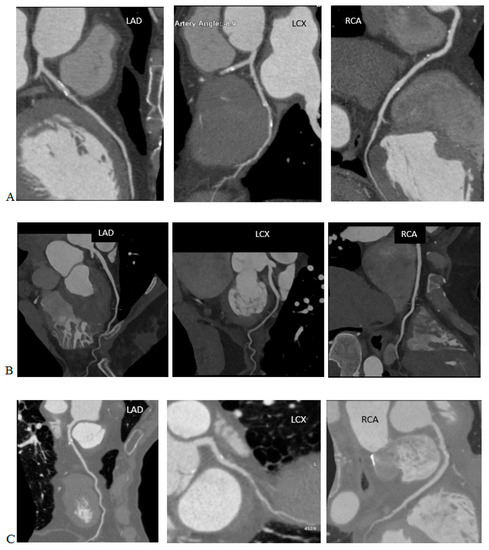

Radiation Doses in Cardiovascular Computed Tomography

by Bartłomiej Kędzierski, Piotr Macek, Barbara Dziadkowiec-Macek, Krystian Truszkiewicz, Rafał Poręba and Paweł Gać

Life 2023, 13(4), 990; https://doi.org/10.3390/life13040990 - 11 Apr 2023

We discussed the contemporary views on the effects of ionising radiation on living organisms and the process of estimating radiation doses in CT examinations and the definitions of the CTDI, CTDIvol, DLP, SSDE, ED. We reviewed the reports from large analyses on the [...] Read more.

We discussed the contemporary views on the effects of ionising radiation on living organisms and the process of estimating radiation doses in CT examinations and the definitions of the CTDI, CTDIvol, DLP, SSDE, ED. We reviewed the reports from large analyses on the radiation doses in CT examinations of the coronary arteries prior to TAVI procedures, including the CRESCENT, PROTECTION, German Cardiac CT Registry studies. These studies were carried out over the last 10 years and can help confront the daily practice of performing cardiovascular CT examinations in most centres. The reference dose levels for these examinations were also collected. The methods to optimise the radiation dose included tube voltage reduction, ECG-monitored tube current modulation, iterative and deep learning reconstruction techniques, a reduction in the scan range, prospective study protocols, automatic exposure control, heart rate control, rational use of the calcium score, multi-slices and dual-source and wide-field tomography. We also present the studies that indicated the need to raise the organ conversion factor for cardiovascular studies from the 0.014–0.017 mSv/mGy*cm used for chest studies to date to a value of 0.0264–0.03 mSv/mGy*cm. Full article